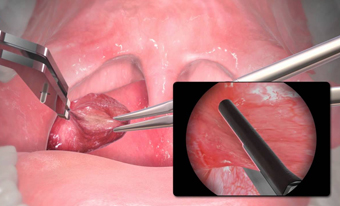

Cirugía de Amígdalas

y Adenoides

Laringe, traquea y cuello

• Amigdalitis, papiloma y reflujo